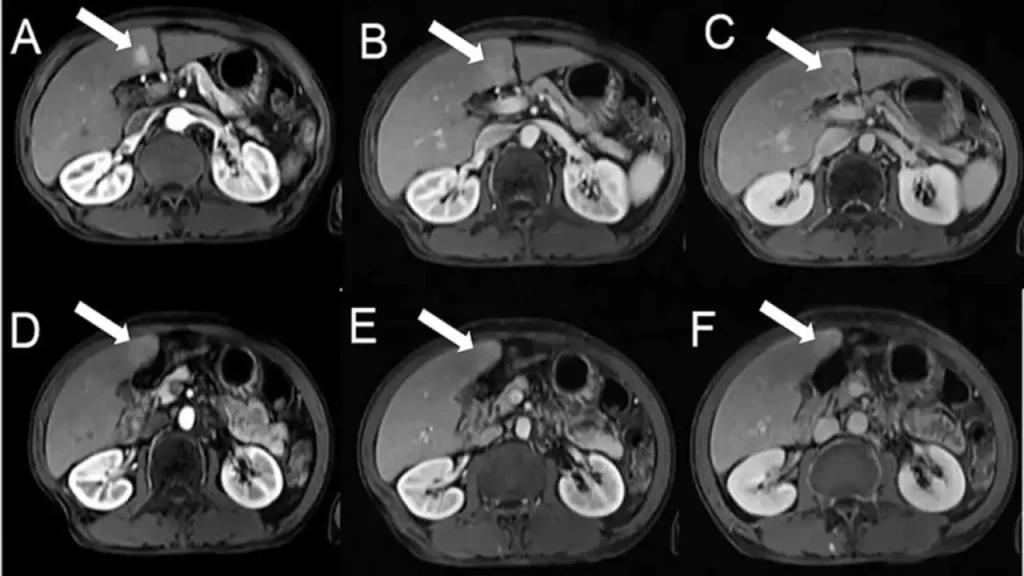

Sudomotor dysfunction may be an early detectable abnormality in diabetic small fiber neuropathy. The aim of this study was to evaluate the efficacy of Sudoscan™ (Impeto Medical, Paris, France) in detecting diabetic neuropathy (DN), in comparison with other standardized tests, in patients with diabetes mellitus (DM).

اختلال عملکرد سودوموتور ممکن است یک ناهنجاری قابل تشخیص زودهنگام در نوروپاتی فیبر کوچک دیابتی باشد. هدف از این مطالعه ارزیابی اثربخشی Sudoscan™ (Impeto Medical، پاریس، فرانسه) در تشخیص نوروپاتی دیابتی (DN)، در مقایسه با سایر آزمایشهای استاندارد، در بیماران مبتلا به دیابت شیرین (DM) بود.